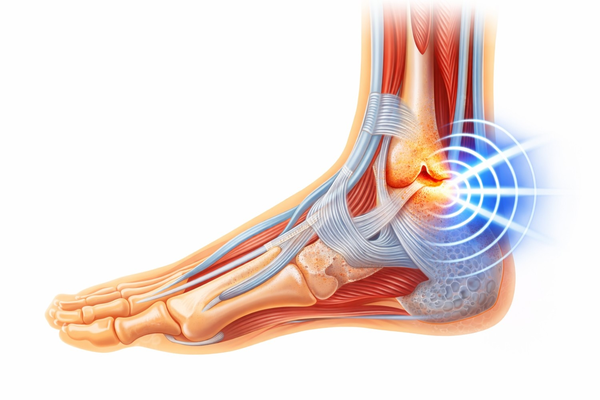

Facet & Joint Support

- Facet joint health

- Spinal joint mobility

- Degenerative joint support